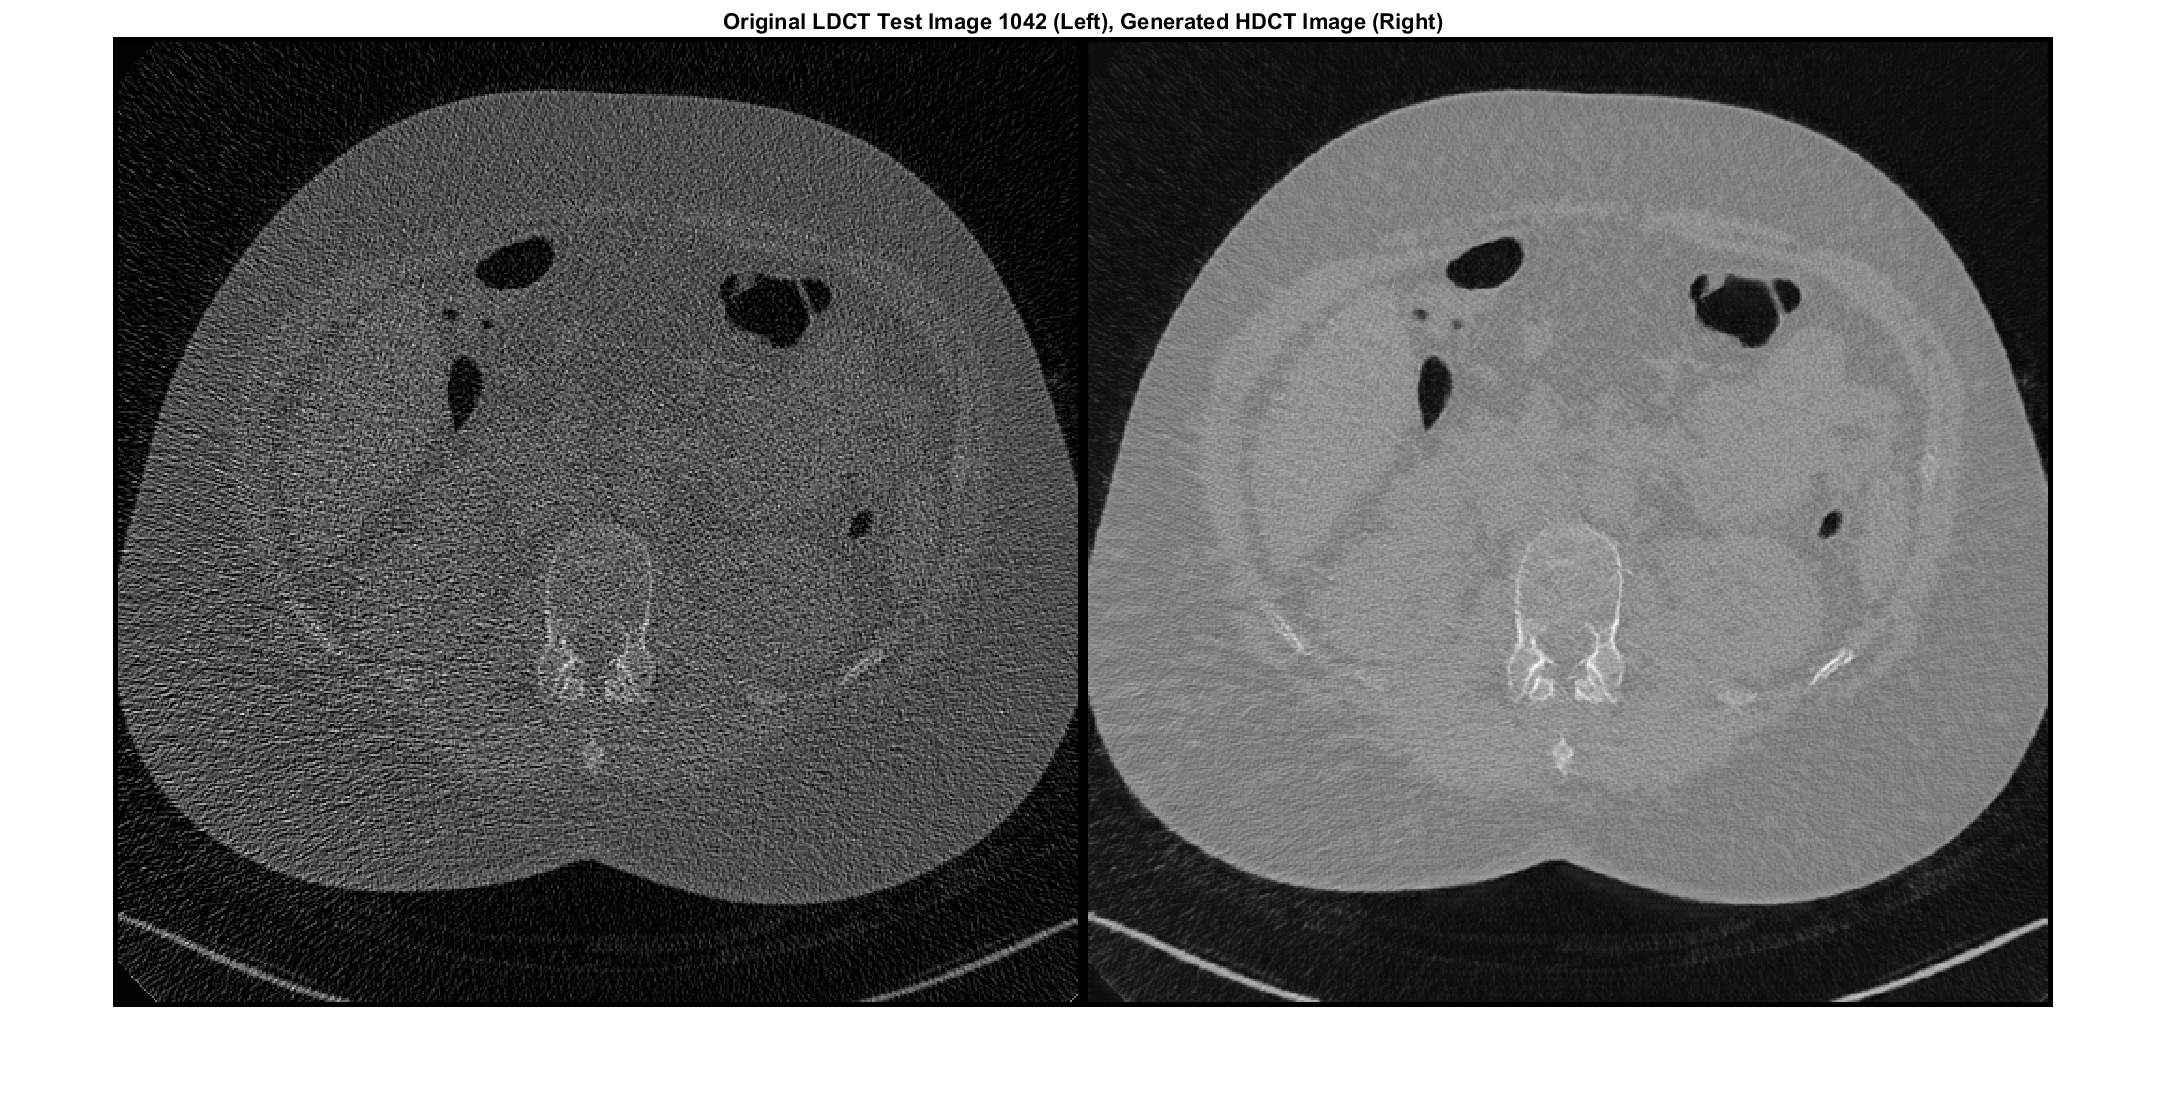

Глубокое обучение использует нейронные сети, чтобы изучить полезные представления функций непосредственно из данных. Например, можно использовать предварительно обученную нейронную сеть, чтобы идентифицировать и удалить артефакты как шум от изображений.

Обучите и примените нейронные сети шумоподавления

Используйте предварительно обученную нейронную сеть, чтобы удалить Гауссов шум из полутонового изображения или обучить вашу собственную сеть с помощью предопределенных слоев.